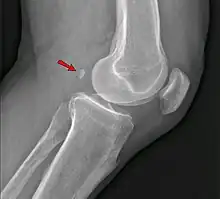

La fabella est un os sésamoïde situé au niveau du genou dans le tendon du chef latéral du muscle gastrocnémien, en arrière du condyle fémoral latéral avec lequel elle s'articule.

La fabella est située dans le tendon du chef latéral du muscle gastrocnémien et apparaît entourée sur son versant antérieur comme postérieur par les fibres tendineuses sur les études histologiques[3]. Elle est reliée dans la plupart des cas à la tête de la fibula par un ligament fabello-fibulaire[3]. Sa taille est variable, comprise entre 4 et 13 mm[3].

Le déplacement de la fabella sur un cliché radiographique est un signe en faveur d'un épanchement intra-articulaire de grande abondance[5].